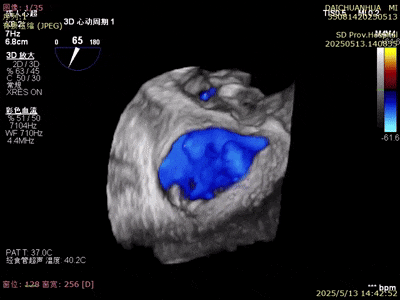

術(shù)前超聲

A3脫垂連枷(脫垂高度9mm,連枷高度:7mm),反流等級(jí)MR 4+(反流寬度11mm),有效瓣環(huán)面積MVA約6.3cm²。前瓣葉長(zhǎng)度23,后瓣葉長(zhǎng)度14.5mm,瓣環(huán)直徑AP 29mm。

術(shù)后超聲

反流變?yōu)檩p度,反流等級(jí)從4+降為1+;

術(shù)后平均跨瓣壓差1mmHg;

夾子夾合量:前葉15mm,后葉10mm;

剩余瓣環(huán)面積:術(shù)后有效瓣環(huán)面積3.7cm²;

二尖瓣3區(qū)可見(jiàn)夾子強(qiáng)回聲,位置固定。

術(shù)前術(shù)后對(duì)比

術(shù)前

術(shù)后